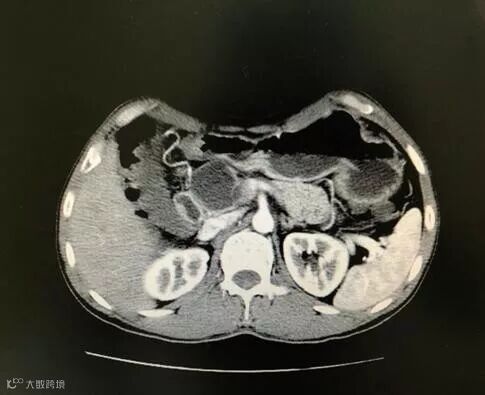

不查不知道,一查吓一跳。影像学提示:胰腺头颈部囊性肿物,考虑假性囊肿可能大,并胰腺体尾部萎缩,不除外囊腺瘤,考虑胰腺占位性病变(病理结果显示:胰头中分化管状腺癌)。普外科副主任邱振雄团队决定为其行胰十二指肠切除术。